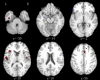

Results: Less gray matter in the high-risk group relative to controls was observed in anterior cingulate regions, left amygdala, and right insula. Lower gray matter volumes in FES compared with controls were also found in the anterior cingulate and right insula but not the amygdala. Lower gray matter volumes in the chronic group were most extensive, incorporating similar regions to those found in FES and high-risk groups but extending to superior temporal gyri, thalamus, posterior cingulate, and parahippocampal gryus. Subtraction analysis revealed less frontotemporal, striatal, and cerebellar gray matter in FES than the high-risk group; the high-risk group had less gray matter in left subcallosal gyrus, left amygdala, and left inferior frontal gyrus compared with FES. Subtraction analysis confirmed lower gray matter volumes through ventral-dorsal anterior cingulate, right insula, left amygdala and thalamus in chronic schizophrenia relative to FES.

Conclusions: Frontotemporal brain structural abnormalities are evident in nonpsychotic individuals at high risk of developing schizophrenia. The present meta-analysis indicates that these gray matter abnormalities become more extensive through first-episode and chronic illness. Thus, schizophrenia appears to be a progressive cortico-striato-thalamic loop disorder.